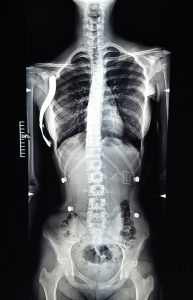

Kinetoterapia în scolioză și cifoză

Metoda tridimensională Schroth

Pacientul scoliotic va beneficia de o terapie adecvată, care înțelege și respecta mecanismul patogenic.

Terapia Schroth este o metoda de corecție posturală 3D activă combinată cu respirație rotațională și corecția percepției posturale.

Metoda Schroth stopează și chiar reduce curbura scoliotică, îmbunătățește aspectul estetic al spatelui, creste capacitatea respiratorie, previne intervenția chirurgicală.